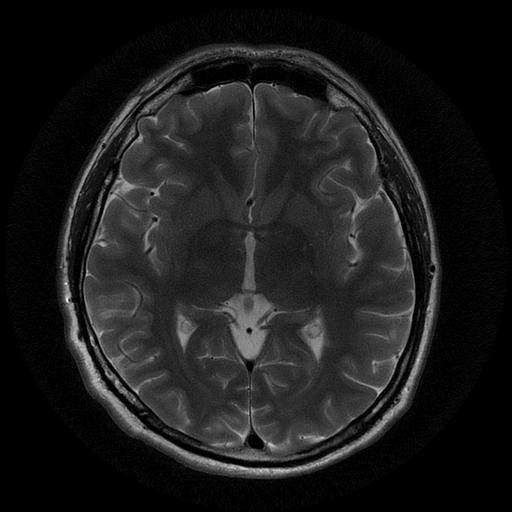

Демиелинизирующие заболевания мозга: МРТ изображения